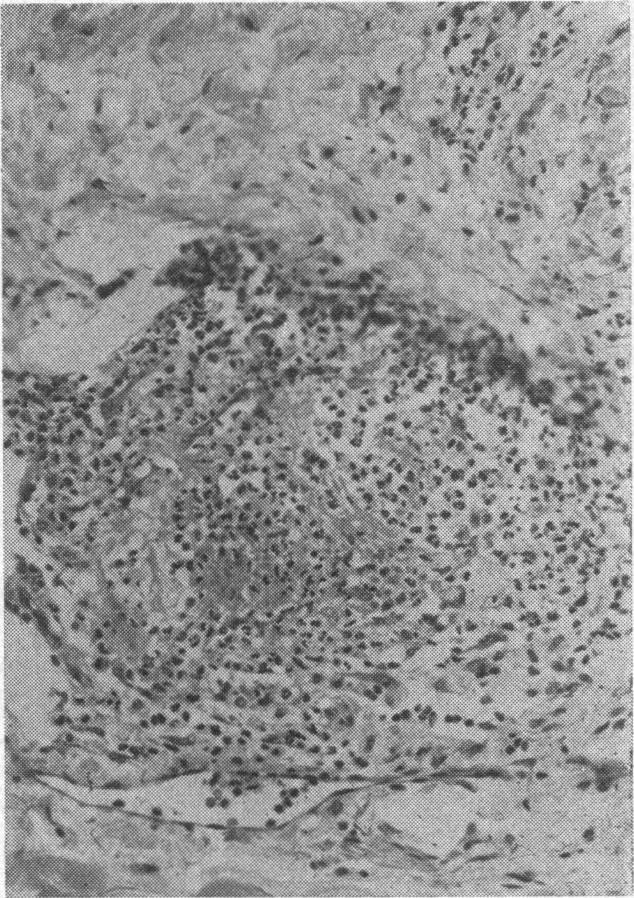

Acute arteritis with digital gangrene.

https://cdn.ncbi.nlm.nih.gov/pmc/blobs/9d88/1863866/5a87c3bcfba5/procrsmed00044-0080-c.jpg

https://cdn.ncbi.nlm.nih.gov/pmc/blobs/9d88/1863866/3a5c3e63e855/procrsmed00044-0080-a.jpg

https://cdn.ncbi.nlm.nih.gov/pmc/blobs/9d88/1863866/2f164af8c611/procrsmed00044-0080-b.jpg

Cutaneous polyarteritis nodosa.皮肤型结节性多动脉炎